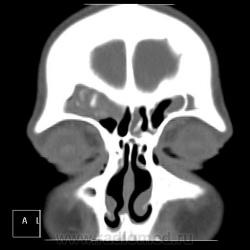

После пары менингитов на фоне синусита решили перебдеть. И вроде не зря... КТ: плотность содержимого в правой лобной пазухе 35-120 ед.Н. (мягкотканное с обызвествлением), в основной пазухе - 24 ед.Н (гнойной жидкости).

И пристеночный гайморит, и двусторонний этмоидит, и ринит, и односторонний сфеноидит, и фронтит, и очень тонкая костная пластинка между основанием передней черепной ямки и больной лобной пазухой - может быть реакция оболочек мозга...

По страшному снимку моему толком не видно, а вот на КТ множественные и разнообразные перегородки в пазухах видны хорошо. Я могу уверенно сказать только о следах жидкости в правой верхнечелюстной пазухе и субтотальном заполнении гомогенной жидкостью левой половины основной пазухи. Остальное, на мой взгляд, утолщение слизистой. Но на 100% утверждать не буду. В правой лобной я предполагаю (и только!) полипоз.

Вроде всё сказали…, но добавлю. Мне кажется, фронтит не односторонний. Эти плотные включения в правой, полипы и есть? Основных (клиновидных) пазух у каждого человека две, как и всех прочих. По обзорному снимку вижу левосторонний этмоидит. А по КТ не вижу. на каких кадрах он есть?

хр.фронтит: справа с образованием обызвествленных полипообразных образований,слева- в виде утолщения слизистой оболочки. Решетчатый лабиринт клиновидной кости занят патологическим содержимым жидкостной плотности(?) с обеих сторон. Основная пазуха: справа - пристеночное утолщение слизистой, слева - тотальное заполнение. Определяется утолщение слизистой верхнечелюстных пазух, видимо воспалительного характера.